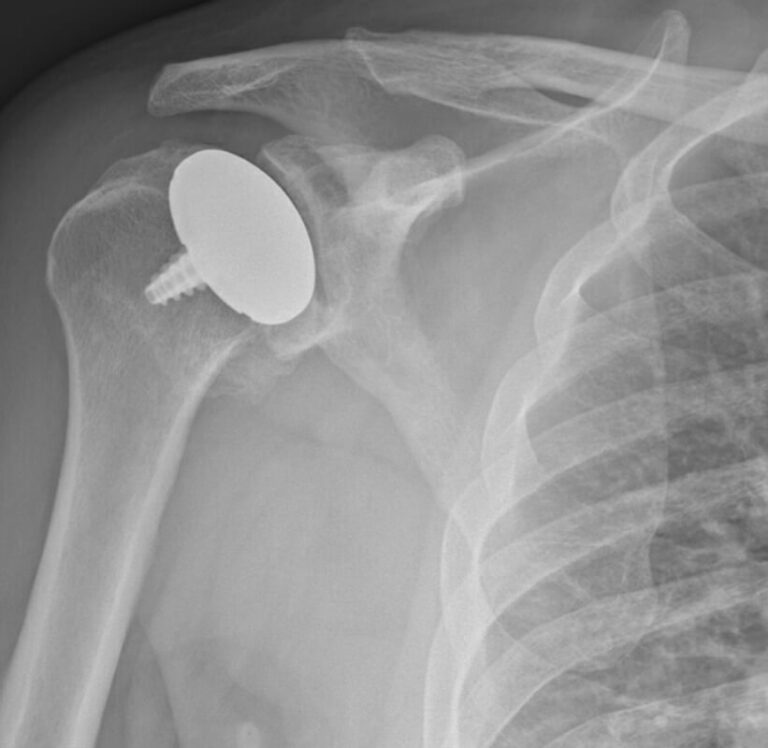

Arthrosurface, HemiCap Large